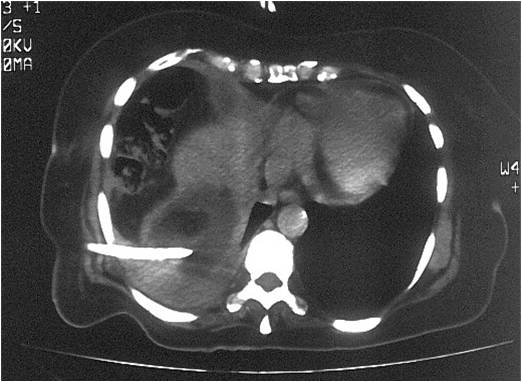

- Abscess post right hemicolectomy

- Successful placement and drainage